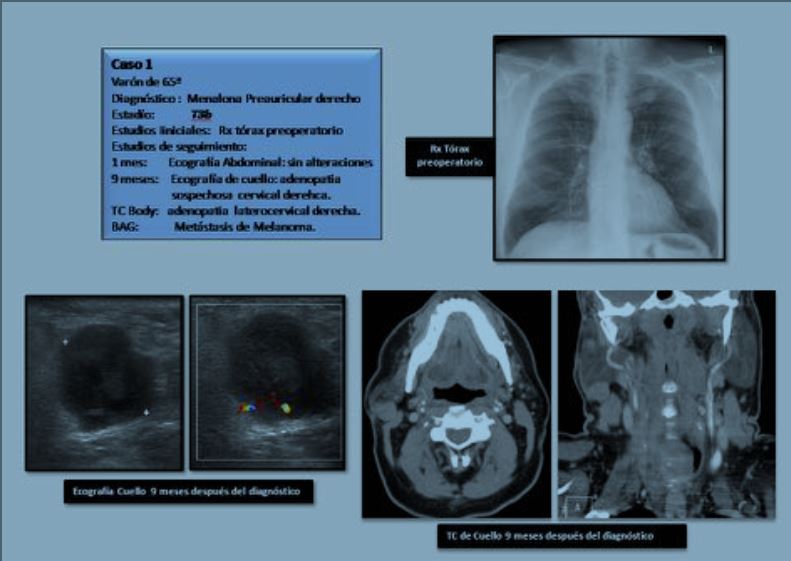

PRUEBAS DE IMAGEN EN EL DIAGNÓSTICO Y SEGUIMIENTO DEL MELANOMA CUTÁNEO

Objetivos Docentes

• Analizar la utilización de las pruebas de imagen en el abordaje del melanoma cutáneo.

• Recomendar un protocolo de pruebas de imagen en el diagnostico y seguimiento del melanoma cutaneo, siguiendo criterios internacionales.